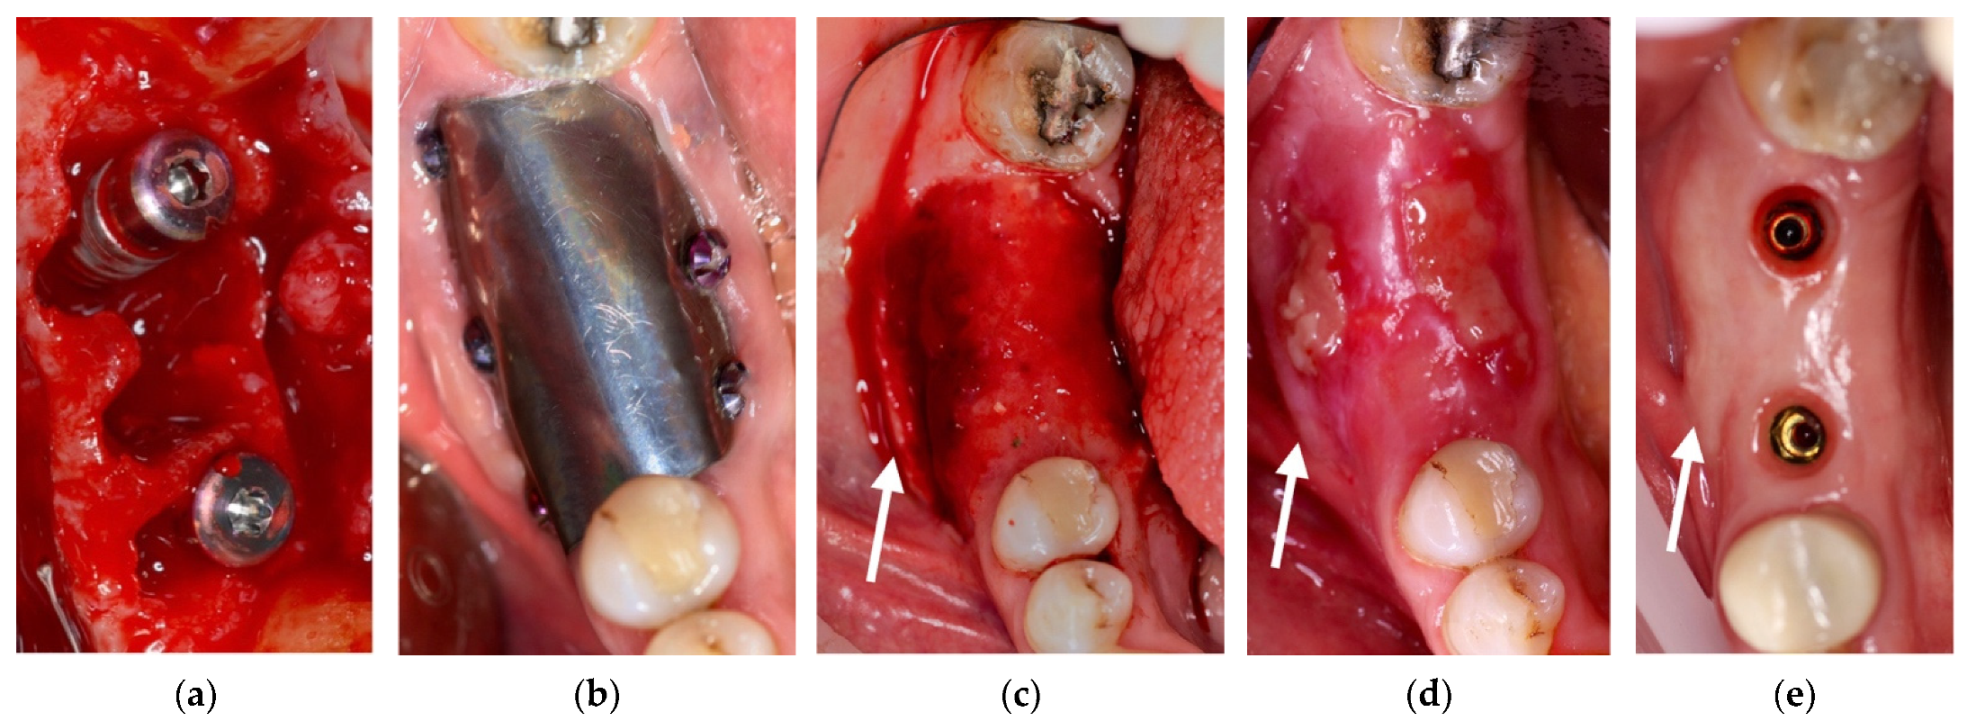

4.2. Clinical Case n.2.

4.3. Clinical Case n.3.

4.4. Clinical Case n.4.

4.5. Clinical Case n.5.